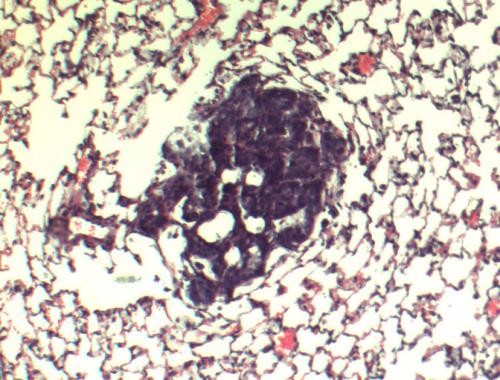

Los estudios fueron corroboradas mediante el tejido de cáncer de mama humano. Un hallazgo adicional en el tejido humano mostró una correlación directa entre la agresividad del tumor y una abundancia de la enzima de la molécula 27HC. También señalaron que 27HC podría hacerse en otros lugares en el cuerpo y se transporta al tumor.

«El peor de los tumores, tiene mucho mas de esta enzima «, dijo el autor principal, Erik Nelson, Ph.D., socio postdoctoral en Duke. Nelson dijo que los estudios de expresión génica revelaron una posible asociación entre la exposición 27HC y el desarrollo de resistencia a los antiestrógeno tamoxifeno. Sus datos también pone de relieve cómo el aumento 27HC puede reducir la eficacia de los inhibidores de la aromatasa, que están entre las terapias contra el cáncer de mama con más frecuencia.

«Este es un hallazgo muy importante», dijo McDonnell. «Tumores de mama humanos, debido a que expresan esta enzima para hacer 27H , están haciendo una molécula similar al estrógeno que pueden promover el crecimiento del tumor. En esencia, los tumores han desarrollado un mecanismo para poder usar una fuente diferente de combustible.»